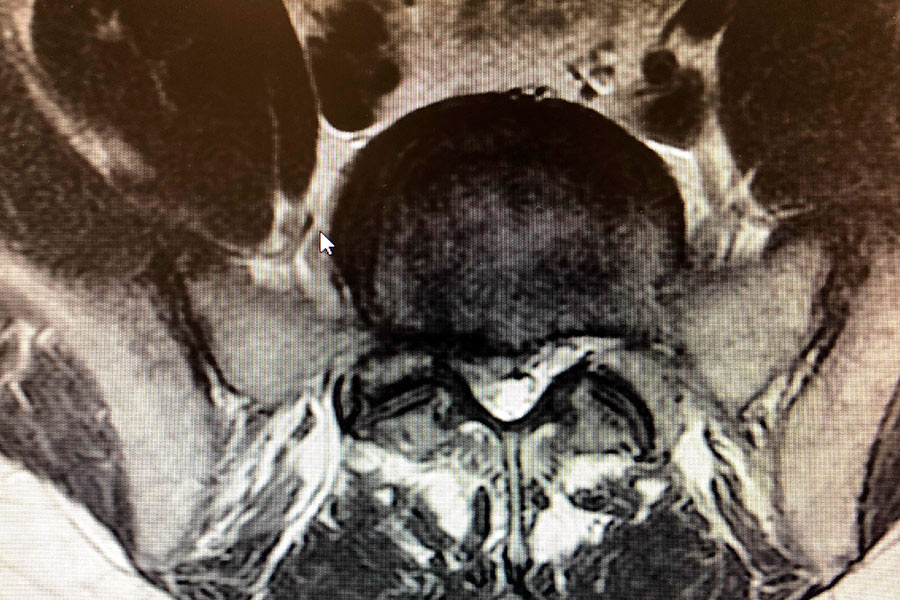

El diagnóstico, desarrollado tras realizar todas las pruebas pertinentes, es de una hernia de pequeño discal L5S1 de pequeño tamaño, situada justamente en la salida de la raíz nerviosa, por lo que hace que el dolor y la pérdida parcial de movimiento sean más acentuados.

hernia-discal-mononivel-endoscopia-de-columna